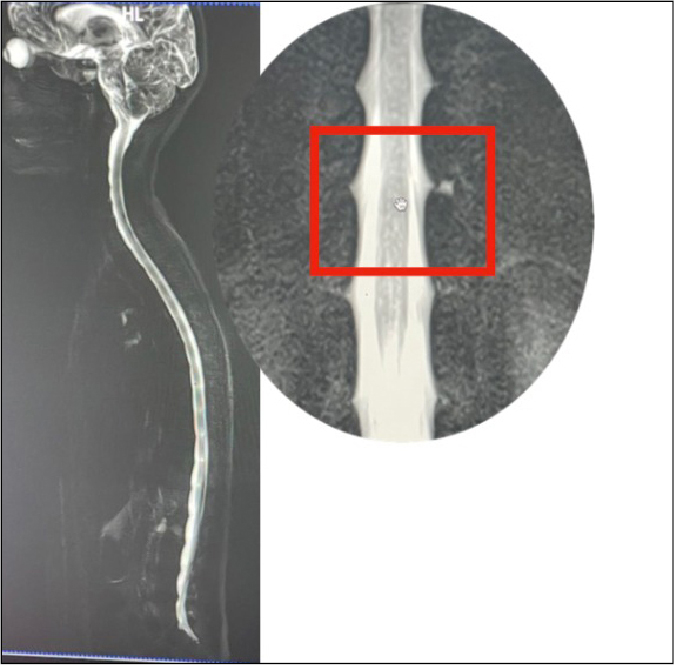

and sagging of brain, the probability of SIH was considered. So, a MRI

myelogram was done, which demonstrated CSF leak at left lower dorsal level

(D11-D12) (Fig. 5). A final diagnosis of SIH was made. Patient was treated with

Figure 5. MRI myelography shows CSF

leak at lower dorsal level (D11-D12).